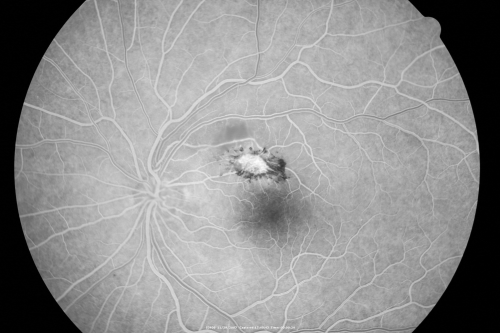

Toxoplasmosis - Inner Retinal - Recurrent - Treated with Bactrim DS

43-year-old man has macular toxoplasmosis. He has responded nicely to Bactrim OS: 20/60